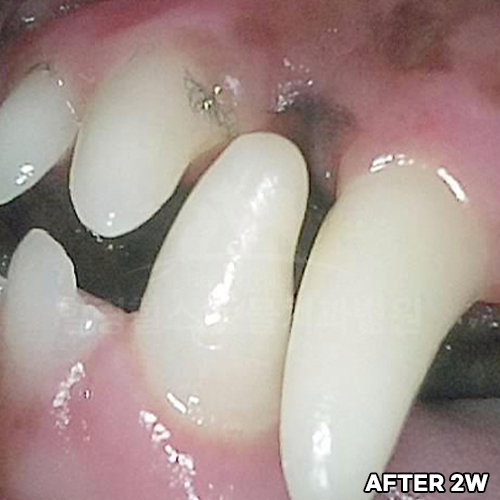

[강아지 치아의 구멍 레진치료 후 2주 경과]